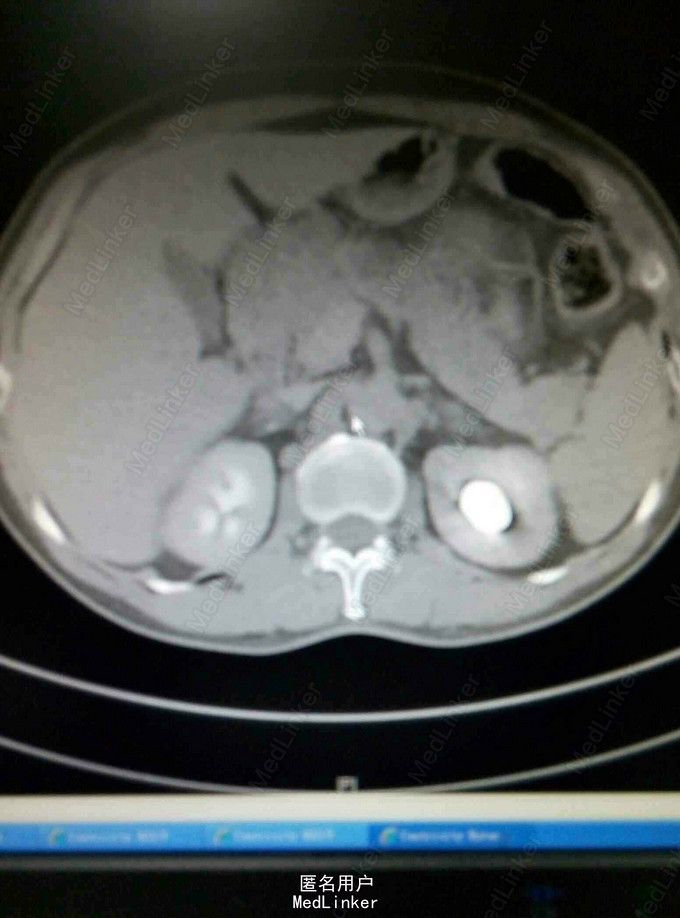

左肾结石一例

男,60岁。左腰不适二周。二周前自觉左腰部不适,无肉眼血尿及腰背绞痛。

左肾区有叩痛。尿中白细胞20/hp。

左肾结石,行经皮肾镜取石术。术后效果良好。